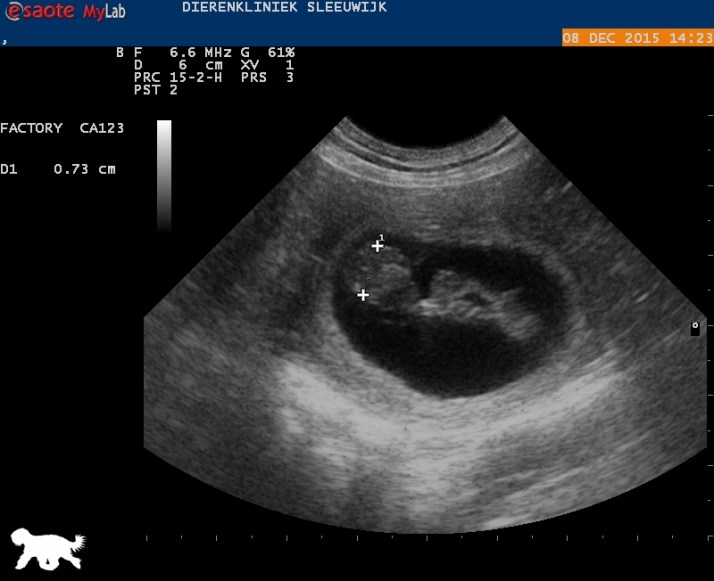

Tussen de witte kruisjes zit het schedeltje van een pup, nu 0.73 cm